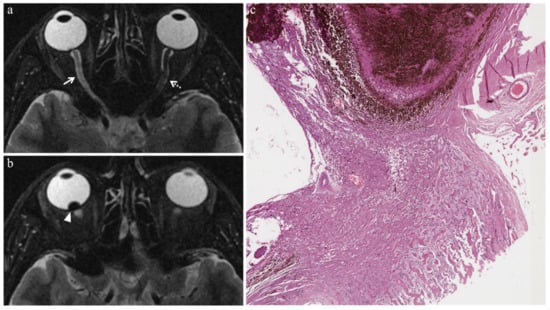

| Vitreous hemorrhage | ![]() Variable signal intensity with possible fluid-fluid level | ![]() High signal of the anterior chamber and vitreous body | ![]() Moderately hyperintense | ![]() High signal |

| Optic nerve degeneration | ![]() Moderately hyperintense | - | - | - |